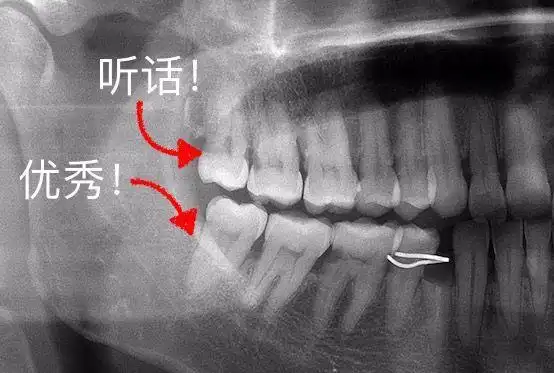

什么样的智齿需要拔来来来教你一分钟自检智齿隐患

不同智齿生长示意图